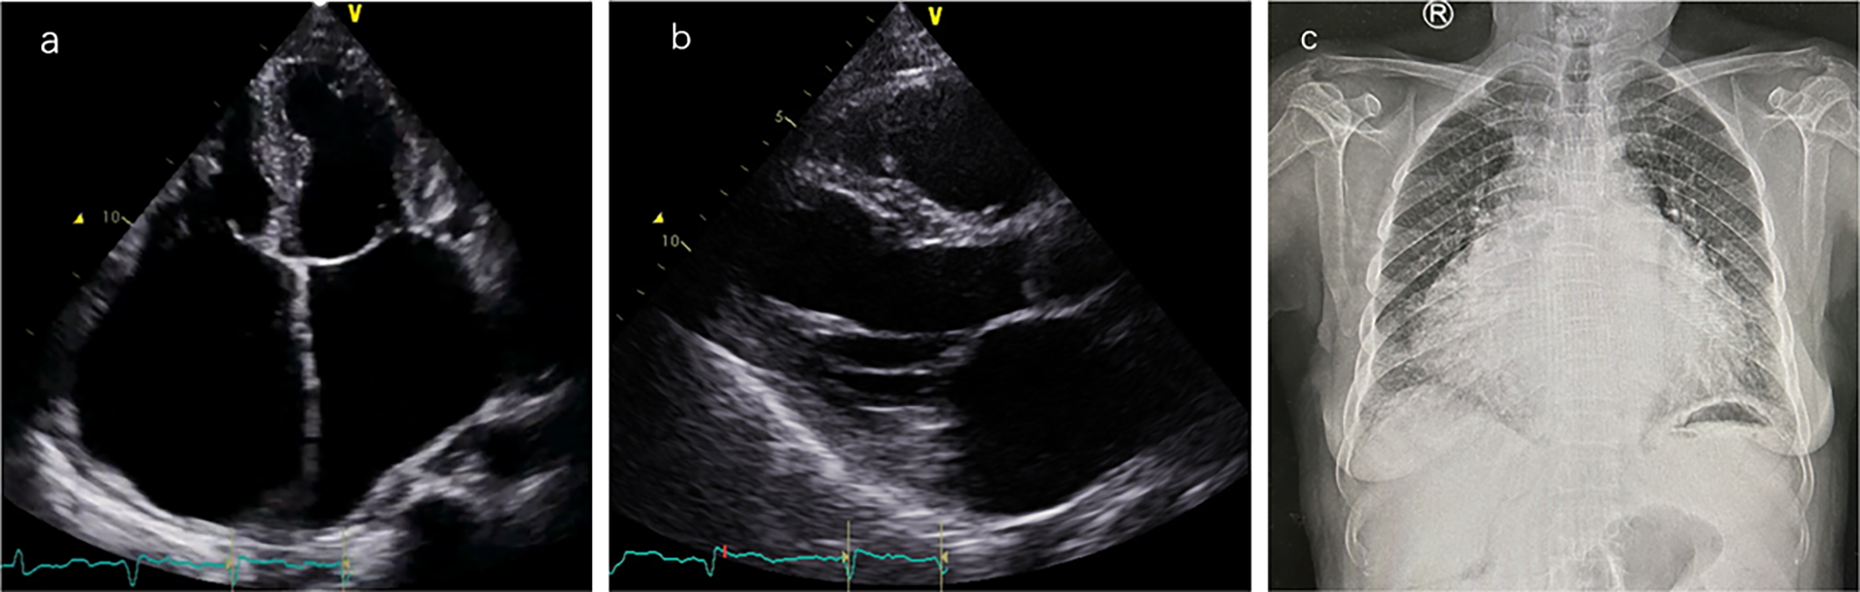

Laboratory tests showed brain natriuretic peptide (BNP) 845 pg/ml and high-sensitivity cardiac troponin I (hs-cTNI) 9.0 ng/L. Echocardiography (UCG) and chest x-ray (Figure 2) revealed global cardiac enlargement (left atrium: anteroposterior diameter 6.4 cm, superior-inferior diameter 8.9 cm, transverse diameter 5.9 cm; right atrium: superior-inferior diameter 9.2 cm, transverse diameter 6.6 cm with an interatrial membrane; left ventricle: end-diastolic diameter 5.8 cm, end-systolic diameter 3.3 cm, posterior wall thickness 1.1 cm, interventricular septum 1.0 cm; right ventricle: anteroposterior diameter 2.4 cm, transverse diameter 5.1 cm), left ventricular ejection fraction 73.7%, severe mitral and tricuspid regurgitation, and an inferior vena cava diameter of 3.6 cm. Septal defect or pulmonary artery stenosis was not found. ECG indicated atrial fibrillation with a ventricular rate of 117 bpm (Figure 3). 1,530 premature ventricular contractions (PVCs) of various morphologies and 4 short runs of ventricular tachycardia were recorded by Holter ECG throughout the day (Figure 3). Furthermore, the patient reported no history of alcohol, drug, or tobacco use, and there was no diagnosis of hypertension. While coronary imaging could not be performed due to the patient's personal preference, bilateral carotid artery ultrasound revealed no atherosclerotic plaques, suggesting a low likelihood of coronary artery disease as a contributing factor. Whole exome sequencing was performed due to suspicion of NSML, revealing a heterozygous pathogenic variant in PTPN11, exon 12, c.1403 C>T (p.Tyr468Met) in the blood samples of both the patient and her son (Figure 4). However, this mutation was not detected in her daughter's blood sample (Figure 4). Genetic testing was not performed on her siblings. Other pathogenic genetic alterations related to cardiomyopathy and arrhythmias were not found to have significant relevance, especially genes for the Rasopathies and the cardiovascular phenotype based on the American College of Medical Genetics and Genomics and the Association for Molecular Pathology guidelines (5). The patient was treated with oral anticoagulants, beta-blockers, and diuretics. Symptoms improved, and the patient was discharged with a follow-up plan. The first follow-up visit was conducted after 15 months. The patient's heart rate is well-controlled, with a mean ventricular rate of 79 beats per minute on Holter monitoring, which indicated 24 h of atrial fibrillation and 26 premature ventricular contractions. The left ventricular end-diastolic diameter remained unchanged at 5.6 cm, leading us to conclude that the likelihood of tachycardia-induced cardiomyopathy is low.

Figure 2

Cardiac imaging findings. (a) Apical four-chamber view: the left atrium has a vertical diameter of 8.9 cm and a transverse diameter of 5.9 cm; the right atrium has a vertical diameter of 9.2 cm and a transverse diameter of 6.6 cm. (b) Left ventricular long-axis view: left ventricular end-diastolic diameter (LVEDD) is 5.8 cm, left ventricular posterior wall thickness (LVPWT) is 1.1 cm, interventricular septal thickness (IVS) is 1.0 cm, and right ventricular anteroposterior diameter is 2.4 cm. (c) Anteroposterior chest x-ray showed significant heart enlargement.